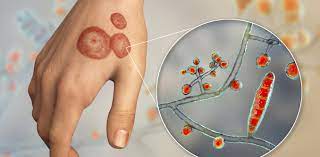

قیمت: 22٬000 تومان - دسته بندی فایل: علوم پزشکیپاورپوینت بیماری های قارچی احشایی

فروش ویژه پاورپوینت حرفه ای بیماری های قارچی احشایی با تخفیف استثنایی فقط 52 هزار تومان تعداد اسلاید: 15 اسلاید